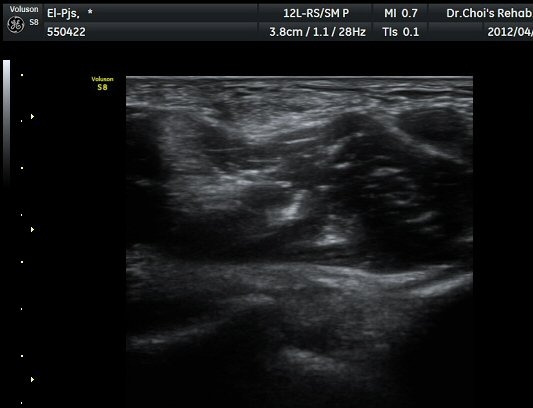

ÆÈ²ÞÄ¡ ¾ÕÂÊ È²µò¸é°Ë»ç¿¡¼­ Á¤»óÀûÀ¸·Î À̵ιڱ٠ÈûÁÙ°ú »ó¿Ïµ¿¸ÆÀÌ °üÂûµÈ´Ù(±×¸² 1).

ŽÃËÀÚ¸¦ ÆÈ²ÞÄ¡ ¸»´ÜÀ¸·Î À̵¿ÇÏ´Ï À̵ιڱ٠ÈûÁÙÀÇ ºñÈÄ¿Í ÈûÁÙ ÁÖÀ§¿¡ Àú¿¡ÄÚ ¼ö¾×Àú·ù°¡ ]

°üÂûµÈ´Ù(±×¸² 2, 3, 4, 5). ŽÃËÀÚ¸¦ ¸»´ÜÀ¸·Î À̵¿ÇÒ ¶§ ŽÃËÀÚ¸¦ ¸Ó¸®ÂÊÀ¸·Î °æ»ç(tilting)½ÃÄѾß

À̵ιڱ٠ÈûÁÙ¿¡ Á÷°¢ ÀÇ ÃÊÀ½ÆÄ Á¶»ç°¡ °¡´ÉÇÏ¿© À̵ιڱ٠ÈûÁÙÀÌ °í¿¡ÄÚ·Î °üÂûµÈ´Ù.